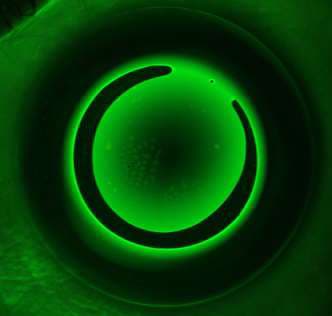

Incomplete reverse curve rings form when a lens fails to align to the peripheral cornea in one meridian. This results in an uneven ring of mid-peripheral steepening, preventing the central fluid pressure from achieving the desired corneal compression. On topography, incomplete reverse curve rings will present as an uneven “bull’s-eye” ring. The reverse curve may be incomplete in only one quadrant (Figure 2) or across an entire meridian (Figure 3).

Such topography patterns can commonly occur without issue and may not require any lens modifications. If the patient’s vision is significantly reduced, consider adjusting the peripheral toricity of the ortho-k design to resolve this issue.